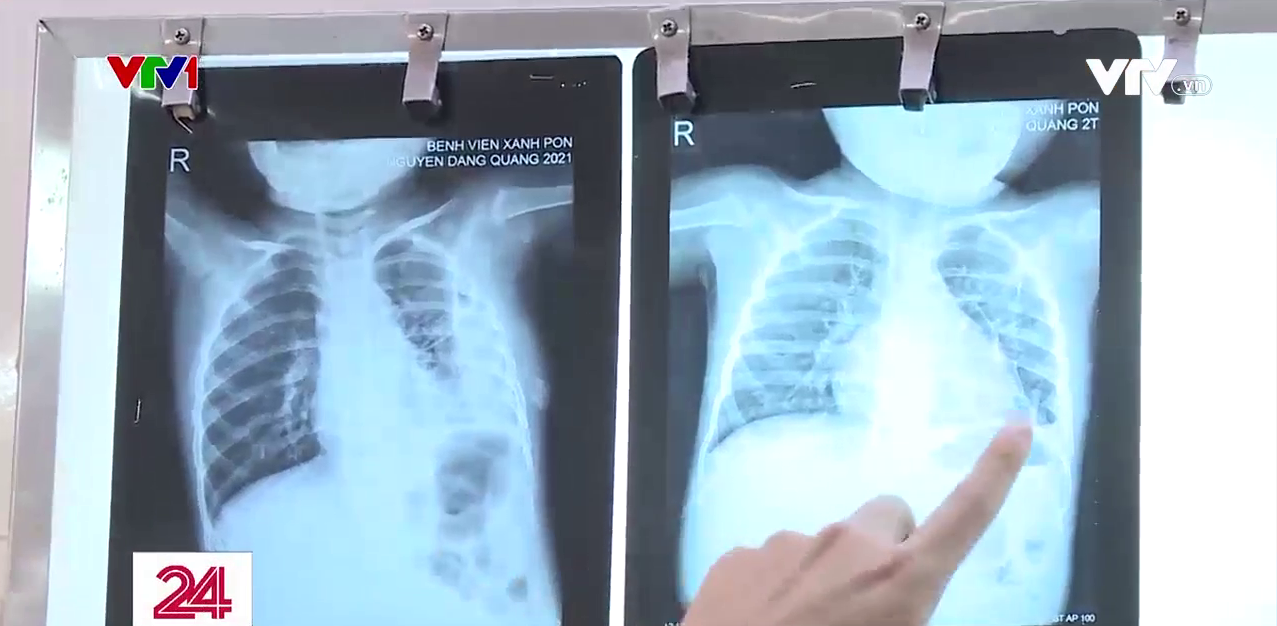

Bệnh nhi này vừa trải qua cơn nguy kịch sau gần 1 tháng điều trị viêm phổi do tụ cầu. Đáng nói trước đó, bé sốt khoảng chục ngày nhưng gia đình vẫn không phát hiện ra bệnh. Chỉ từ nốt nhọt ở gót chân, bệnh nhi xuất hiện tình trạng áp xe phổi, viêm màng phổi.

Chị Đỗ Thảo Ly, TP. Hà Nội cho biết: “Chụp phim đã bị mưng mủ trắng hết bên phổi rồi. Chỉ có 2 nốt thôi rất to nên không biết cách điều trị như nào”.

TS.BS. Phan Thị Kim Dung – Phó trưởng khoa Nhi hô hấp, Bệnh viện Đa khoa Xanh Pôn cho biết: “Sẽ tìm thấy những ổ trên da, mụn nhọt do tụ cầu, sau đó trẻ mới có những biểu hiện về hô hấp. Trên da mà có ban hay nhọt như thế, đôi khi cha mẹ không đi khám bệnh thì dễ nhầm lẫn vấn đề liên quan đến virus như chân tay miệng hay ban khác mà đôi khi họ ko biết tưởng là sốt xuất huyết”.